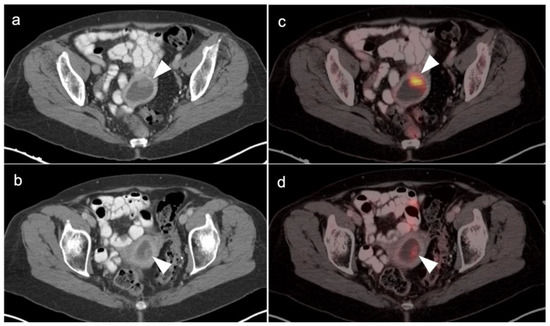

- Zattoni, F.; Incerti, E.; Moro, F.D.; Moschini, M.; Castellucci, P.; Panareo, S.; Picchio, M.; Fallanca, F.; Briganti, A.; Gallina, A.; et al. 18F-FDG PET/CT and Urothelial Carcinoma: Impact on Management and Prognosis—A Multicenter Retrospective Study. Cancers 2019, 11, 700. [Google Scholar] [CrossRef]

- Girard, A.; Reyes, H.V.; Shaish, H.; Grellier, J.-F.; Dercle, L.; Salaün, P.-Y.; Delcroix, O.; Rouanne, M. The Role of 18F-FDG PET/CT in Guiding Precision Medicine for Invasive Bladder Carcinoma. Front. Oncol. 2020, 10, 565086. [Google Scholar] [CrossRef]

- Tanaka, H.; Yoshida, S.; Komai, Y.; Sakai, Y.; Urakami, S.; Yuasa, T.; Yamamoto, S.; Masuda, H.; Koizumi, M.; Kohno, A.; et al. Clinical Value of 18F-Fluorodeoxyglucose Positron Emission Tomography/Computed Tomography in Upper Tract Urothelial Carcinoma: Impact on Detection of Metastases and Patient Management. Urol. Int. 2015, 96, 65–72. [Google Scholar] [CrossRef]

- Asai, S.; Fukumoto, T.; Tanji, N.; Miura, N.; Miyagawa, M.; Nishimura, K.; Yanagihara, Y.; Shirato, A.; Miyauchi, Y.; Kikugawa, T.; et al. Fluorodeoxyglucose positron emission tomography/computed tomography for diagnosis of upper urinary tract urothelial carcinoma. Int. J. Clin. Oncol. 2015, 20, 1042–1047. [Google Scholar] [CrossRef]